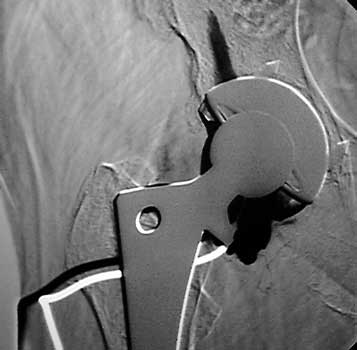

Dry tap secondary to large greater trochanteric bursa, 20

gauge spinal needle placed in bursa under fluoroscopic guidance

Scar with focal area of drainage. Dry tap secondary to large greater trochanteric bursa with

sinus tract draining to skin

Dry tap secondary to sinus tract decompression

Sinus tract draining posteriorly